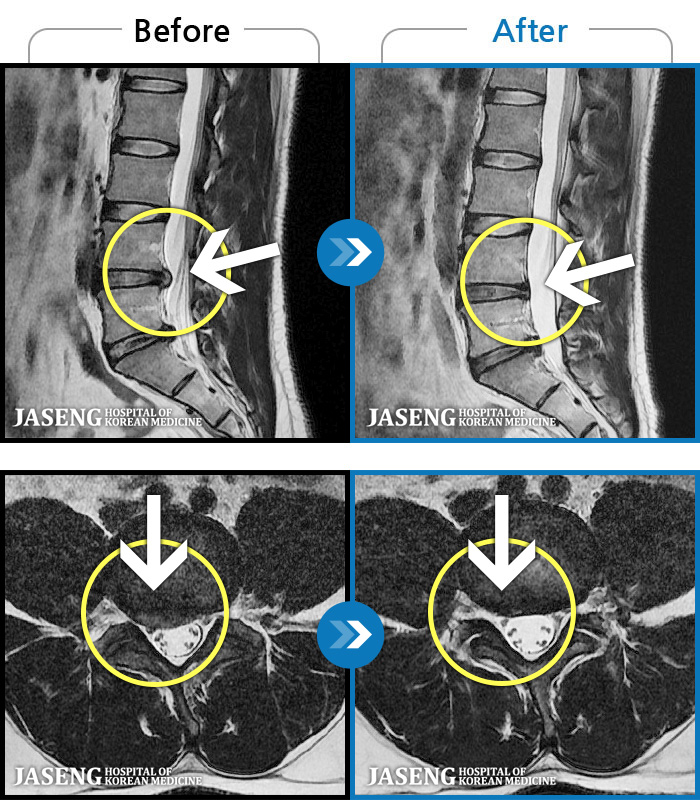

MRI ġ

MRI ũ ʸ Ȯϼ.